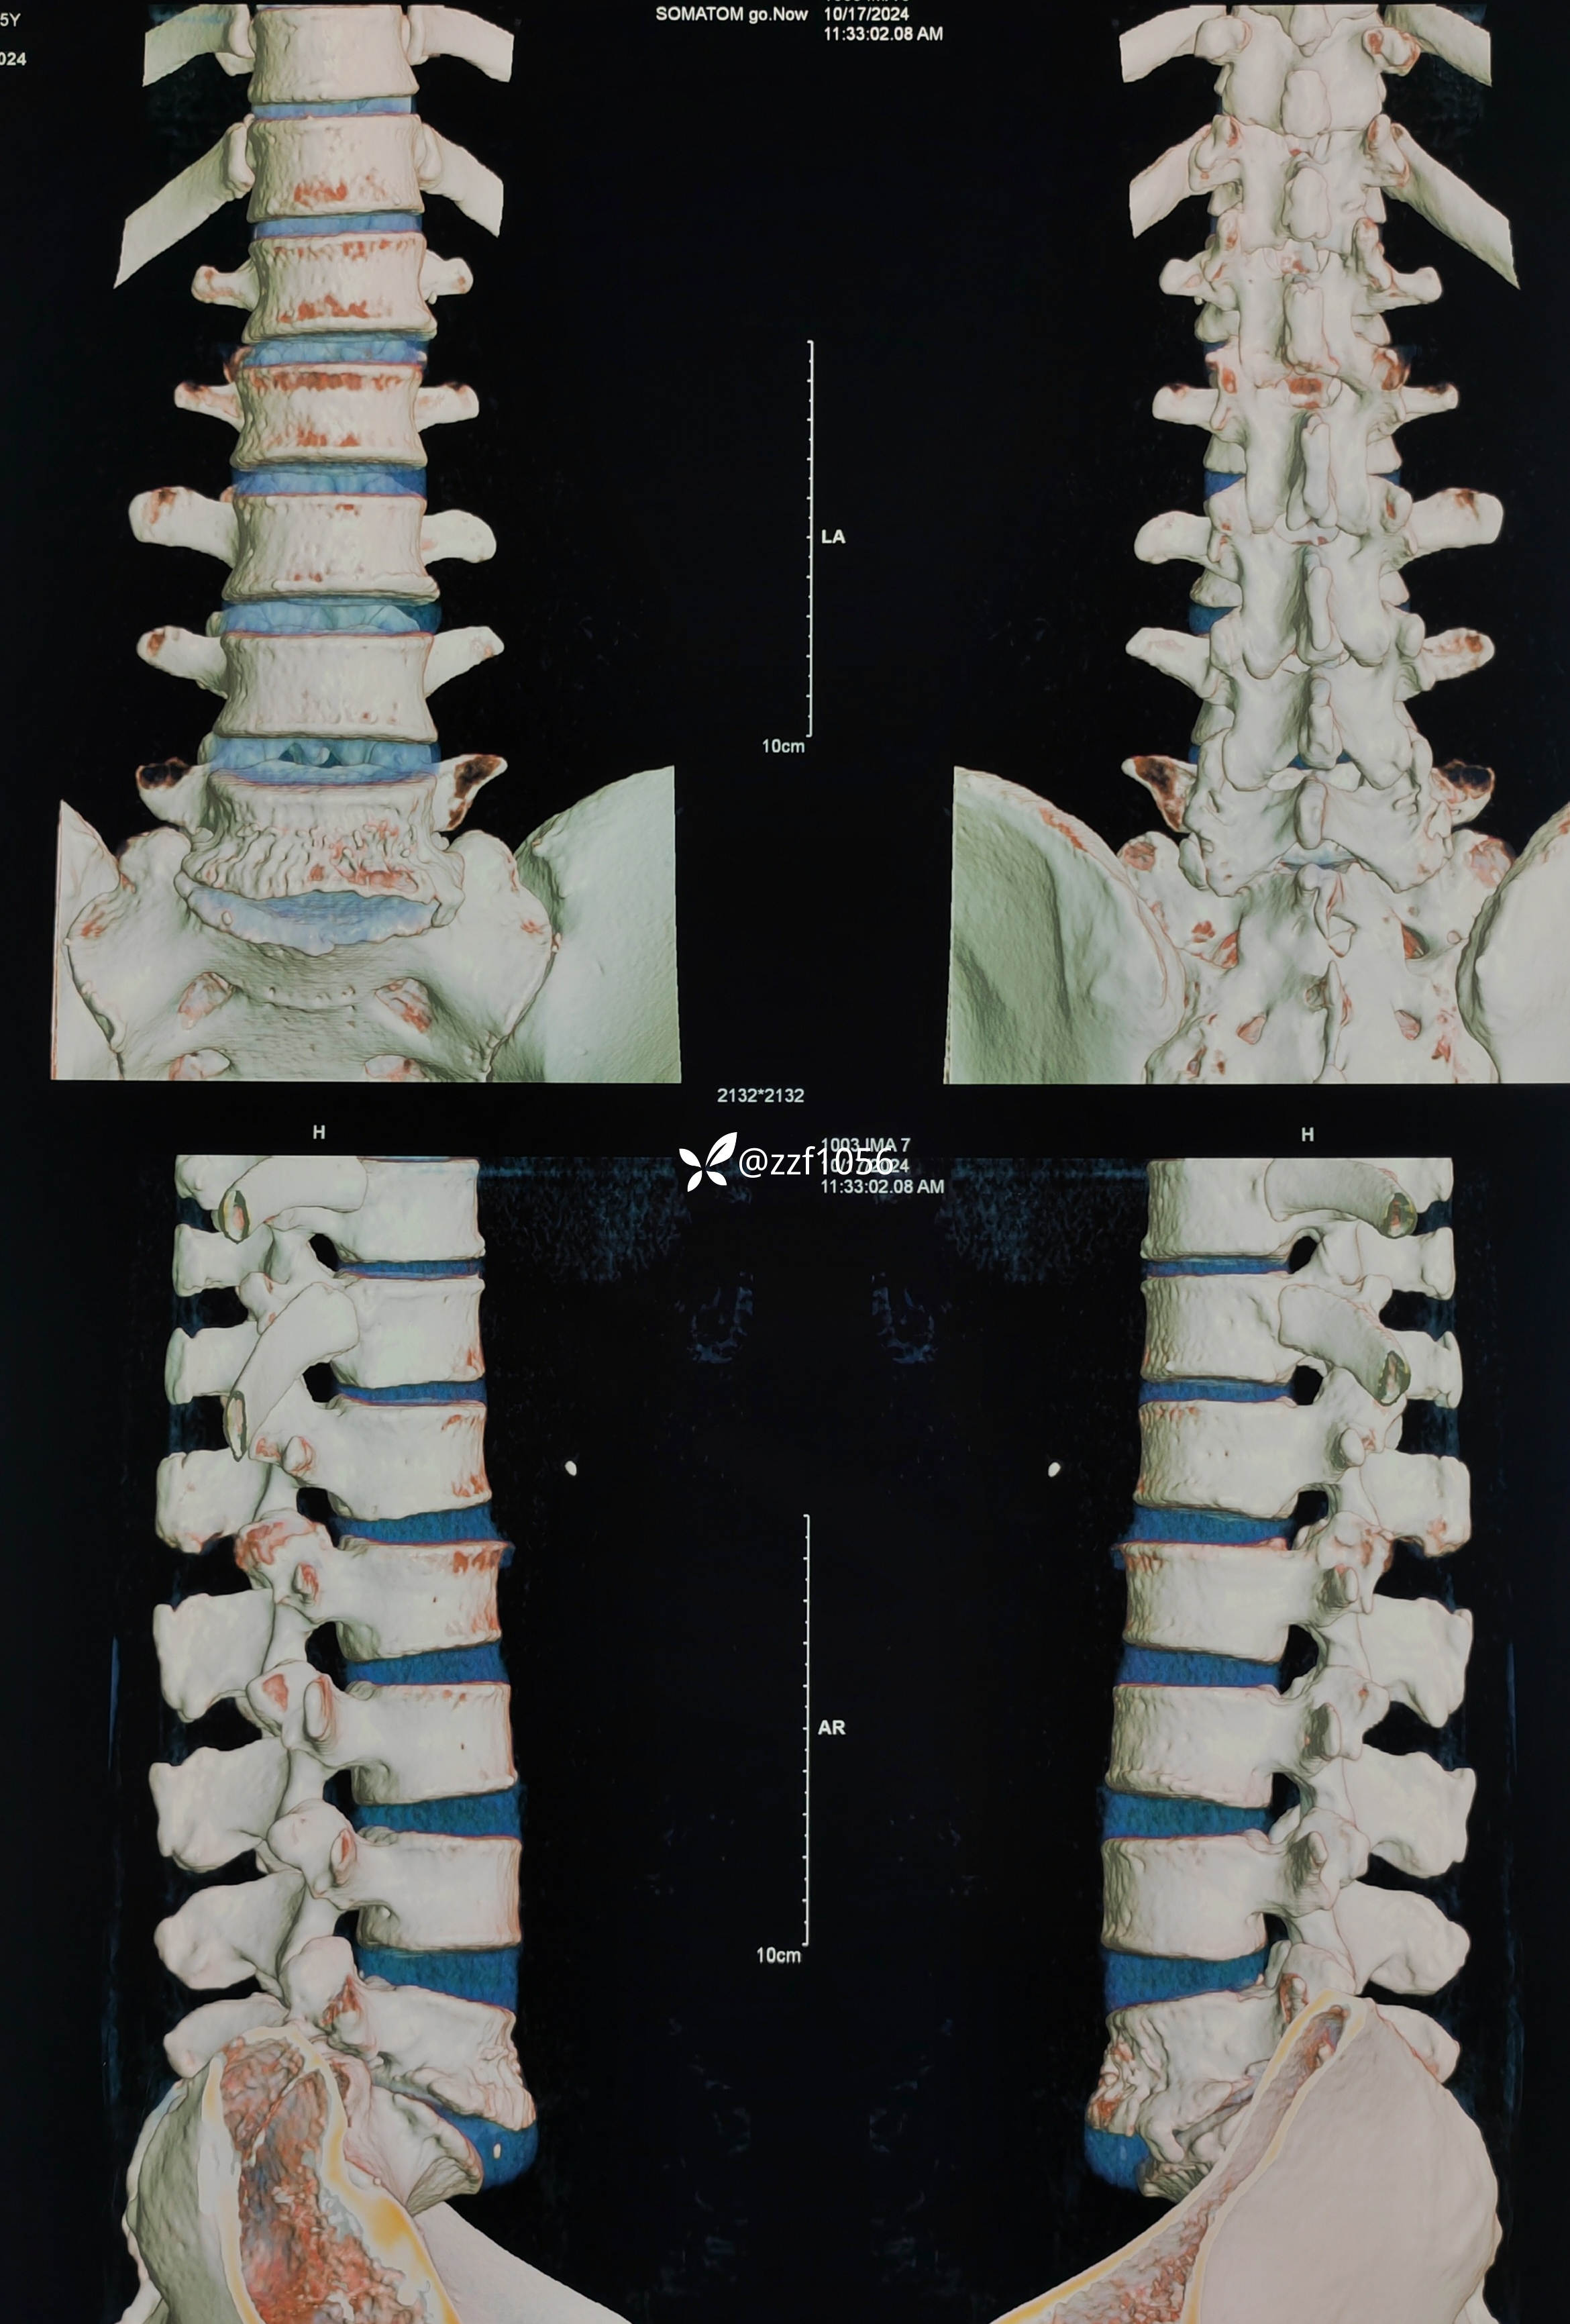

右侧减压彻底,L5S1根松弛,保留了左侧关节突所以撑开有限,使用8mmCage

影像上可看到L5/S1间隙非常狭窄,退变严重,两侧均有神经根激惹,椎间孔狭窄,L5下终板终板炎较重,左下肢无任何症状,右下肢L5S1根症状均存在,建议椎间孔镜下减压L5根和S1根,患者拒绝,因咨询多家医院要求开放融合。